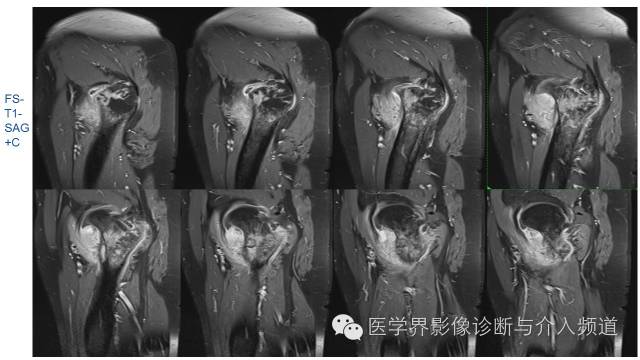

MR平扫及增强示:

右侧股骨上段见不规则形长T1短等T2异常信号,直径约1.5cm,邻近骨皮质破坏,其内骨髓可见斑片状长T1等长T2混杂信号,边界不清,股前方可见软组织肿块,呈长T1等长T2混杂信号,DWI呈明显高信号;注入GD-DTPA后,股骨内病灶呈轻度强化,周围软组织呈明显不均质强化。左侧髋关节诸组成骨对位关系可,未见明显骨质破坏征象,双侧髋关节可见少量斑片状长T2液体信号影。